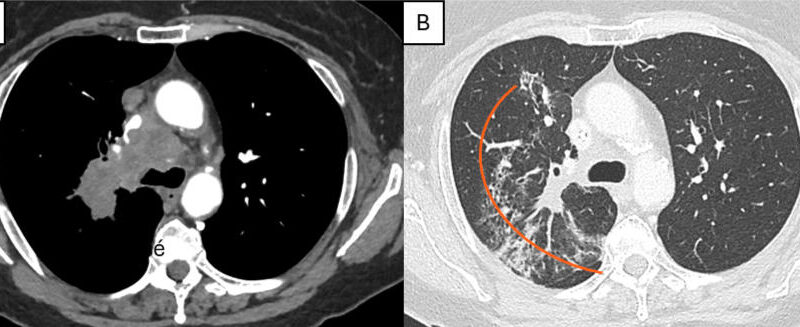

Olivier Humbert / Le projet FEDERATED-PET vise à prédire, avant de mettre en place une immunothérapie, si le patient fait partie des 50 % de patients qui répondront au traitement [1]. L'expression de la cible thérapeutique PDL1, le seul biomarqueur de l’efficacité de l’immunothérapie utilisé en routine aujourd'hui, a beaucoup de faiblesse. Des biomarqueurs TEP peuvent compléter ce biomarqueur biologique, à l'image du volume tumoral de la maladie métastatique, qui a une valeur prédictive très nettement supérieure à celle de l'expression de la cible thérapeutique PDL1 [2]. L'objectif de FEDERATED-PET est de développer une intelligence artificielle capable de chercher sur les images TEP de nouveaux biomarqueurs sans a priori. En sortie, elle créera une combinaison de biomarqu